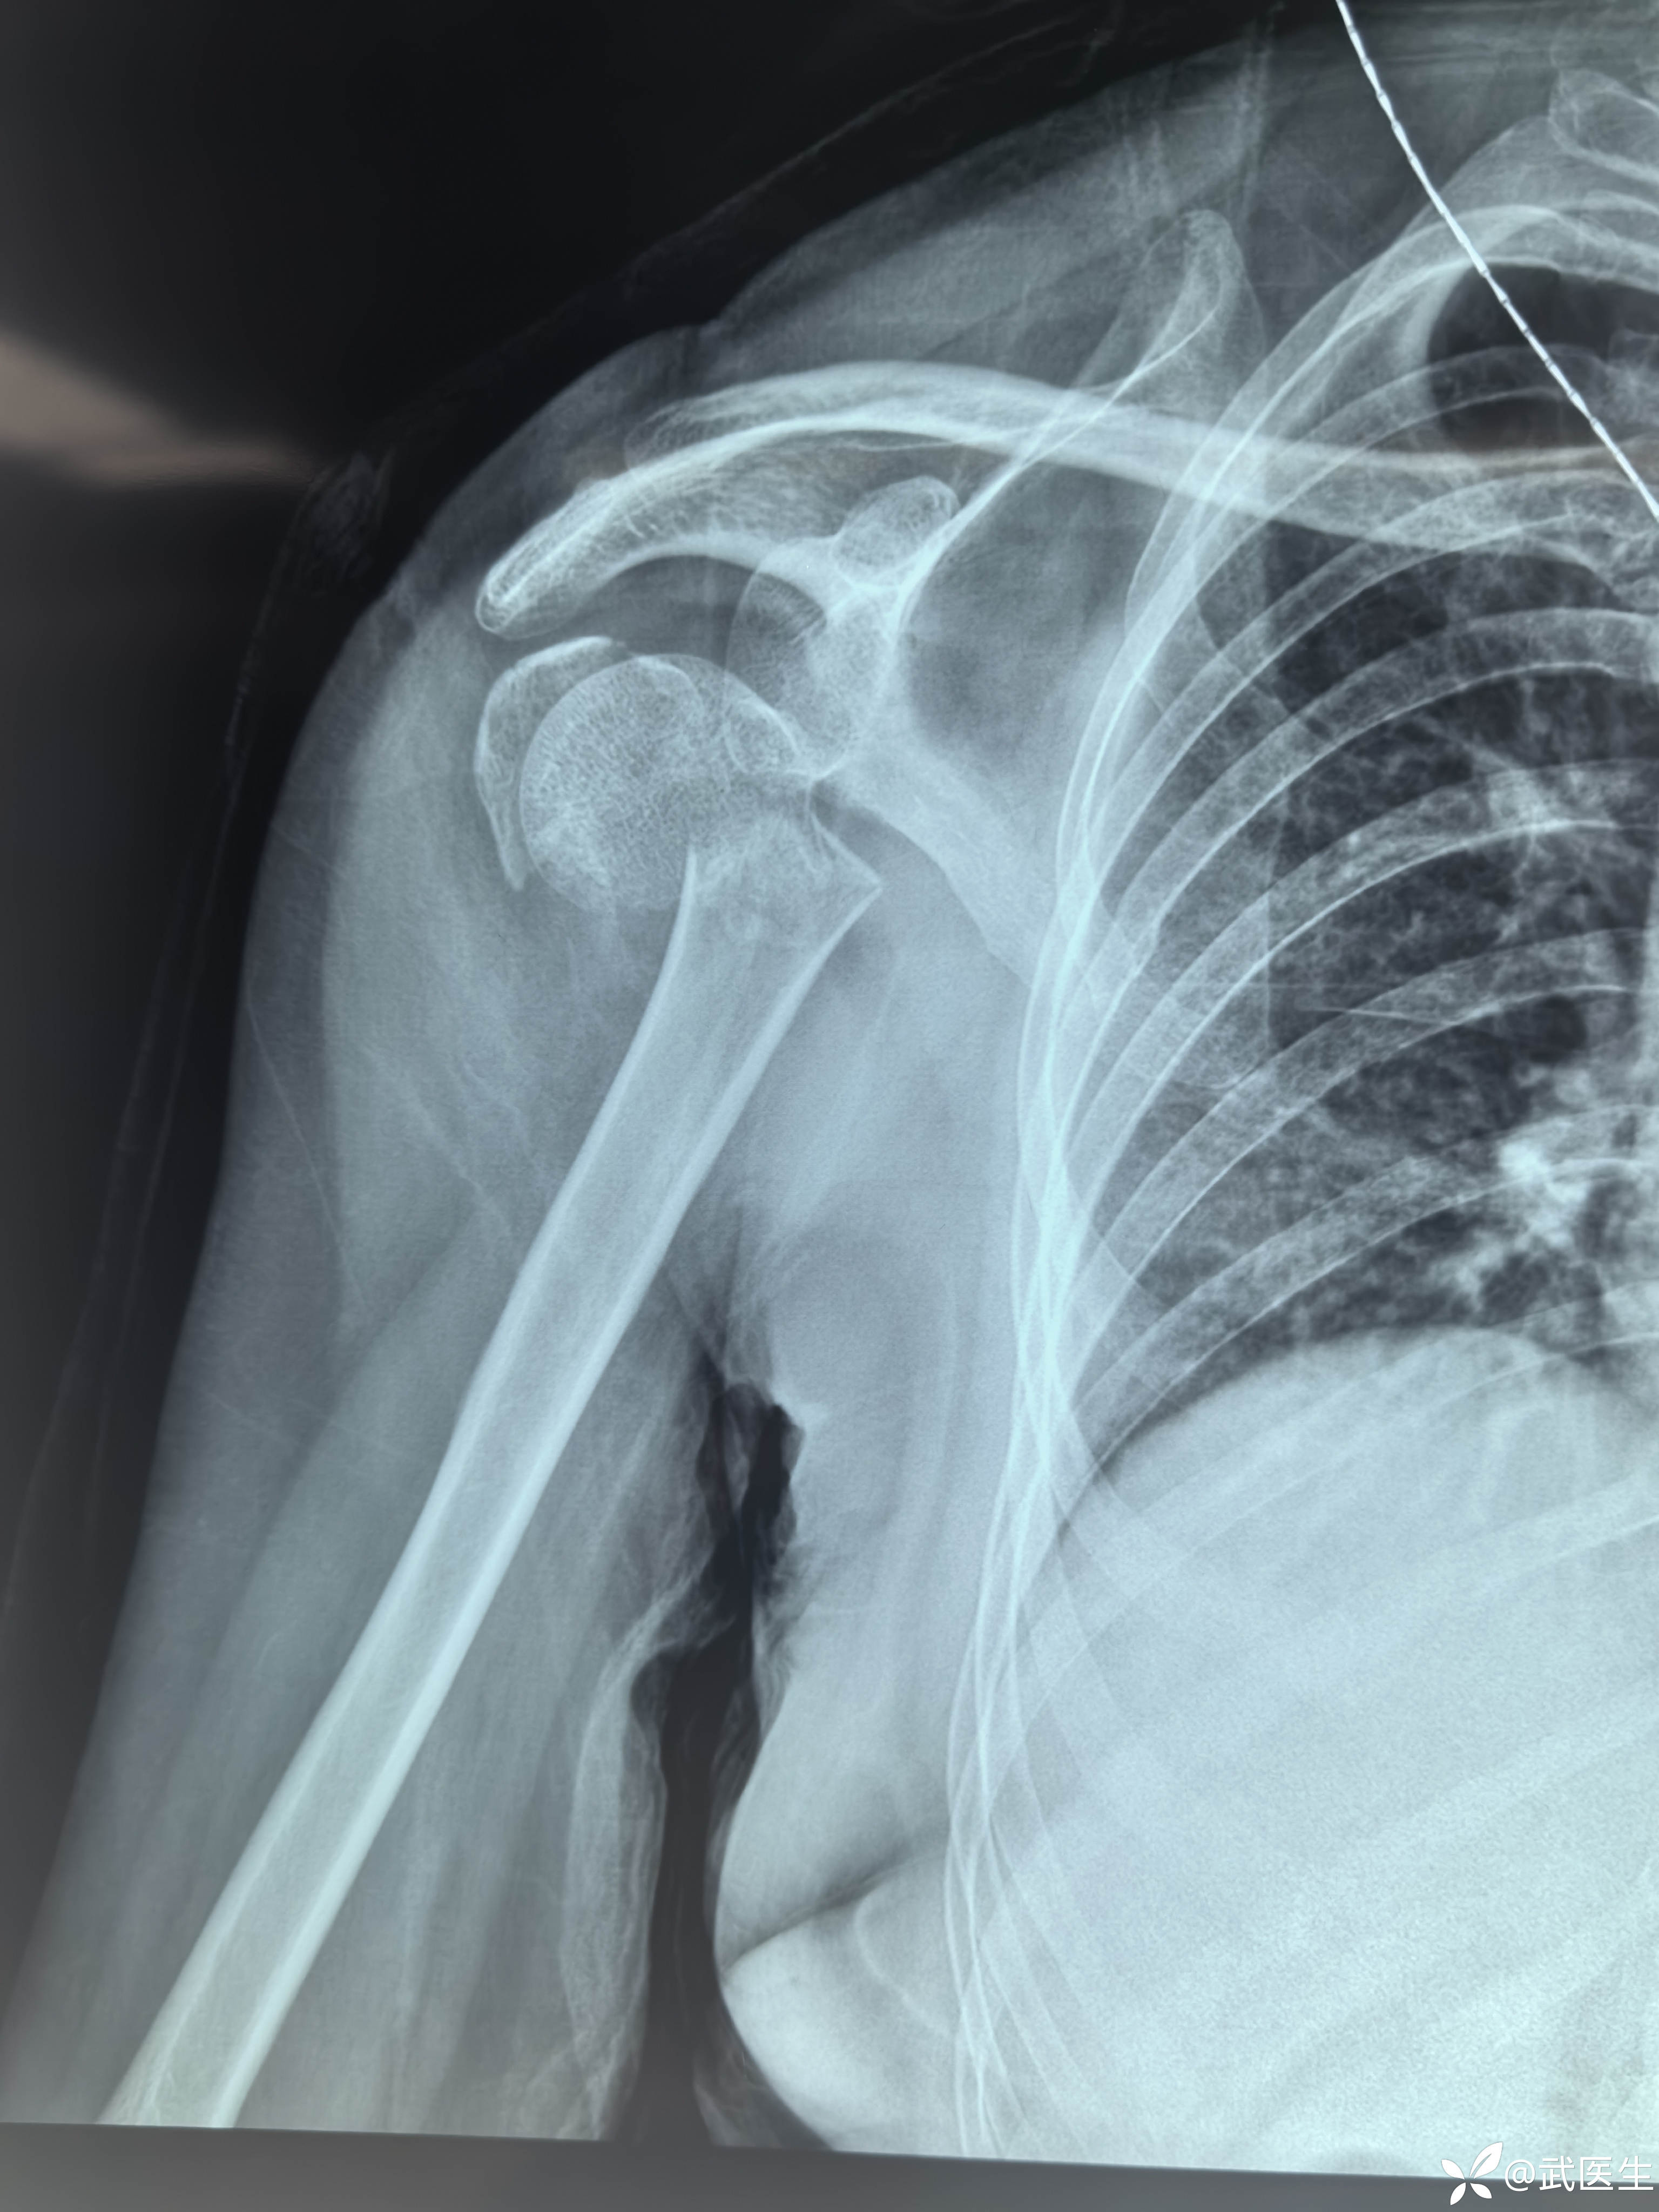

汇报一例肱骨近端四部分骨折脱位

【主诉】:摔伤致右肩,左腕疼痛畸形,头面部皮肤挫伤一小时

【检查】:右肩,左腕皮肤完整,肿胀+++,局部压痛,可扪及骨异常活动及骨擦音,活动受限。头面部多处皮肤擦伤,右眼,额部肿胀+++。

【临床诊断】:右肱骨外科颈四部分骨折脱位,左桡骨远端骨折伴桡腕关节半脱位。钩骨骨折。头面部软组织损伤。